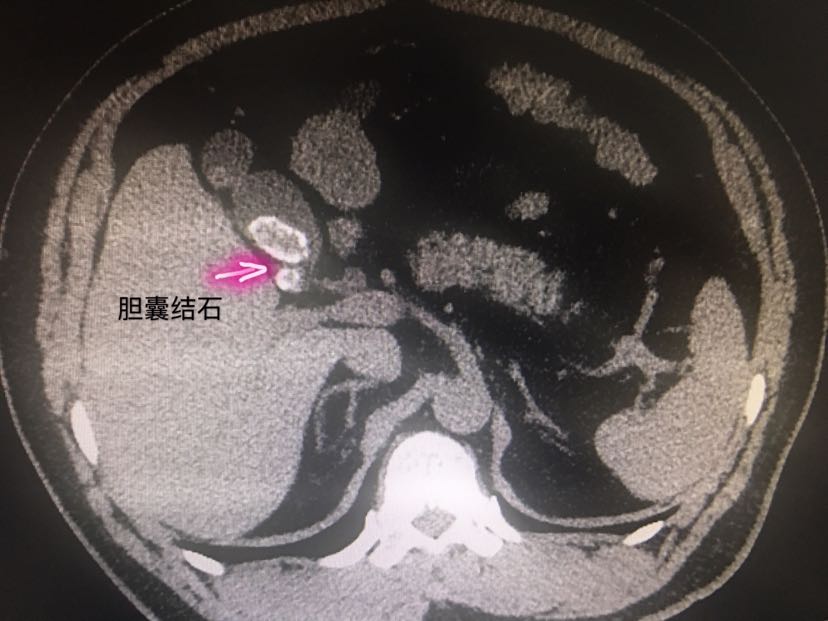

ct提示胆囊结石伴胆囊炎

胆系结石上腹部ct平扫胆囊

部分胆囊结石ct可显影

混合性结石胆色素结石ct表现为高密度,ct值在50hu以上,单发或多发